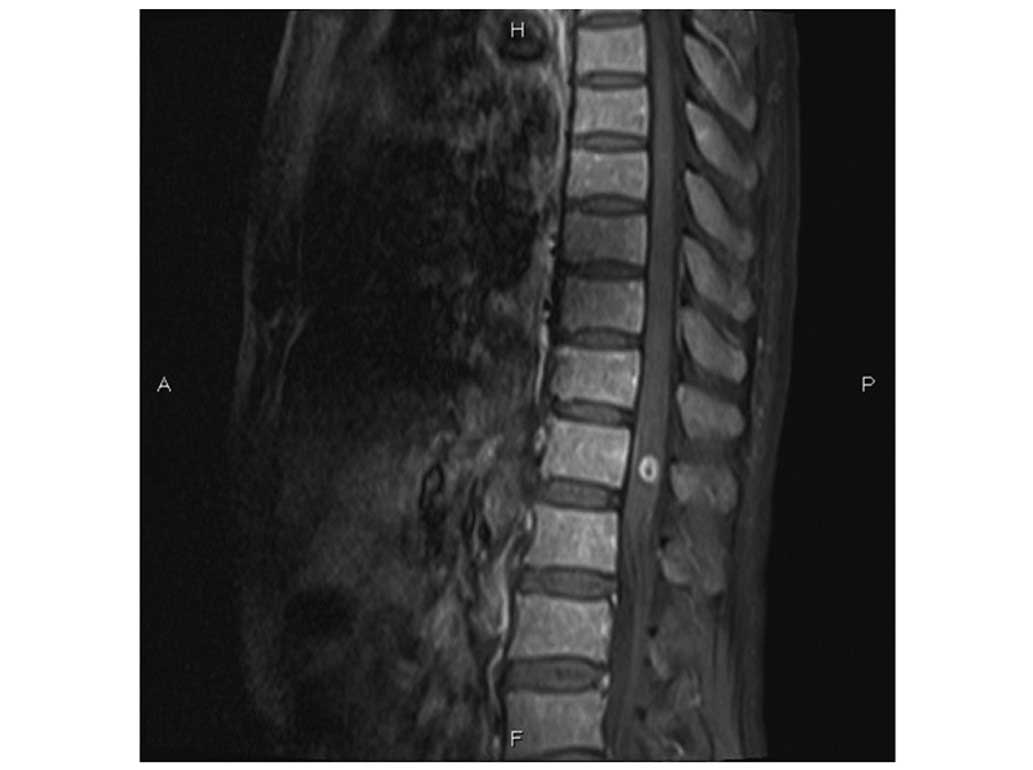

bone marrow following the initial course of chemotherapy. Magnetic

resonance (MR) imaging (MAGNETOM Verio 3.0T; Siemens AG, Munich,

Germany) revealed lymphomatous infiltration at the T12 vertebra

(Fig. 1A). Leukemic infiltration of